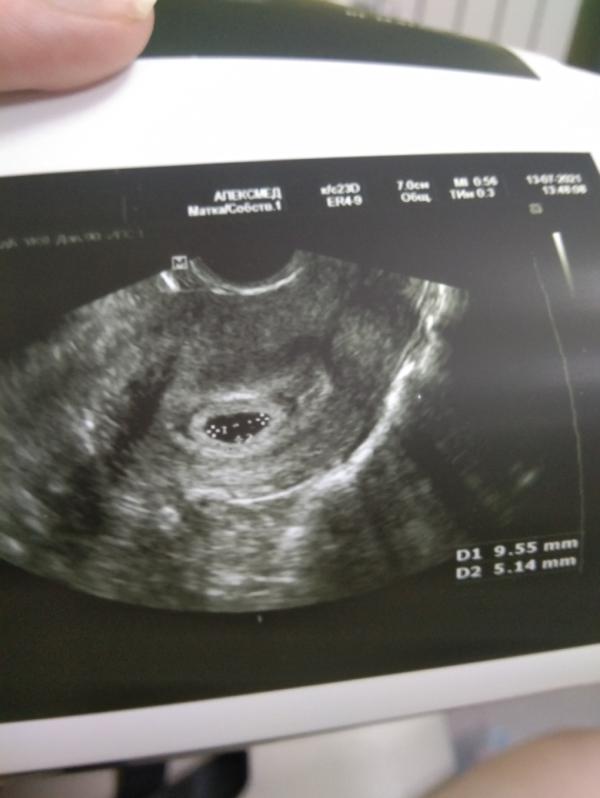

Первое успокоение, первое узи, ждем повторное через 10 дней пока малыша не видно, но то, что беременность маточная, уже радует 😊